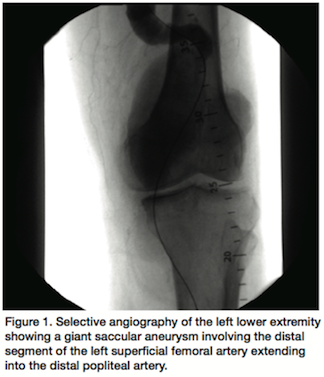

Selective angiography of the left lower extremity revealed a giant saccular aneurysm involving the distal segment of the left superficial femoral artery extending into the distal popliteal artery (Figure 1). The vessel tapered to become normal caliber at the tibioperoneal trunk with single vessel runoff (Figure 2).